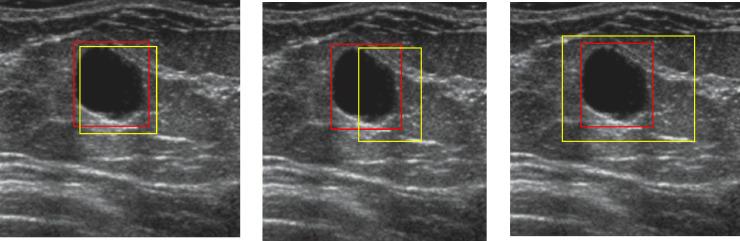

This study aims to develop automatic breast tumor detection and classification including automatic tumor volume estimation using deep learning techniques based on computerized analysis of breast ultrasound images. When the skill levels of the radiologists and image quality are important to detect and diagnose the tumor using handheld ultrasound, the ability of this approach tends to assist the radiologist's decision for breast cancer diagnosis.

MATERIAL AND METHODS

Breast ultrasound images were provided by the Department of Radiology of Thammasat University and Queen Sirikit Center of Breast Cancer of Thailand. The dataset consists of 655 images including 445 benign and 210 malignant. Several data augmentation methods including blur, flip vertical, flip horizontal, and noise have been applied to increase the training and testing dataset. The tumor detection, localization, and classification were performed by drawing the appropriate bounding box around it using YOLO7 architecture based on deep learning techniques. Then, the automatic tumor volume estimation was performed using a simple pixel per metric technique.

乳腺超声图像由泰国玛希隆大学放射科和泰国诗丽吉王后乳腺癌中心提供。数据集包括 655 张图像,其中 445 张为良性,210 张为恶性。应用了几种数据增强方法,包括模糊、垂直翻转、水平翻转和噪声,以增加训练和测试数据集。使用基于深度学习技术的 YOLO7 架构,通过在其周围绘制适当的边界框来进行肿瘤检测、定位和分类。然后,使用简单的像素度量技术进行自动肿瘤体积估计。